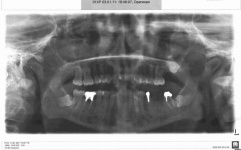

Если Ваш доктор назначает ОПТГ - ортопантомографию, то этот метод позволит получить снимок, на котором будет одномоментное изображение всей зубочелюстной системы как единого функционального комплекса. Благодаря данному методу можно проводить диагностику различных заболеваний зубочелюстной системы: выявление кариеса контактных поверхностей коронковой части и пришеечных отделов зубов, выявление кариеса пришеечных и жевательных поверхностей коронковой части зуба под пломбами, определение локализации деструктивных процессов, анализ количества и характера изгиба корней зубов.